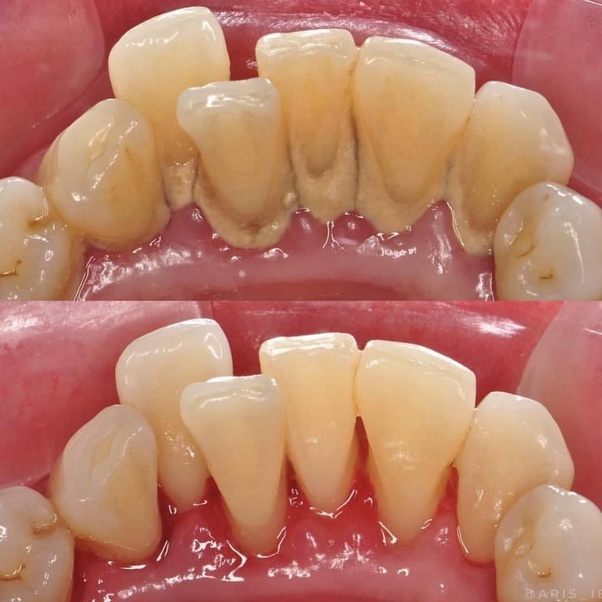

Scaling and polishing is a simple yet powerful procedure designed to remove plaque and tartar from the teeth, while also polishing the tooth surface, leaving it smooth and gleaming. This procedure is not only crucial for maintaining oral hygiene but also for preventing more serious dental issues such as gum disease.

Aarti was hesitant at first but decided to give it a try. On the day of her appointment, she was greeted by a friendly dental hygienist who explained the process in detail, putting her at ease. The scaling process, though slightly uncomfortable, was quick and thorough. It involved the removal of hardened plaque (tartar) from her teeth using specialized tools. Following the scaling, the polishing process began, where her teeth were buffed using a special paste that removed surface stains and left her teeth feeling smooth and clean.

The immediate results were astonishing. Aarti's teeth felt cleaner, her gums healthier, and her smile noticeably brighter. But the benefits extended beyond the physical transformation. The procedure had a profound impact on her confidence. No longer worried about the state of her teeth, Aarti found herself smiling more freely and interacting with her colleagues and clients with renewed assurance.